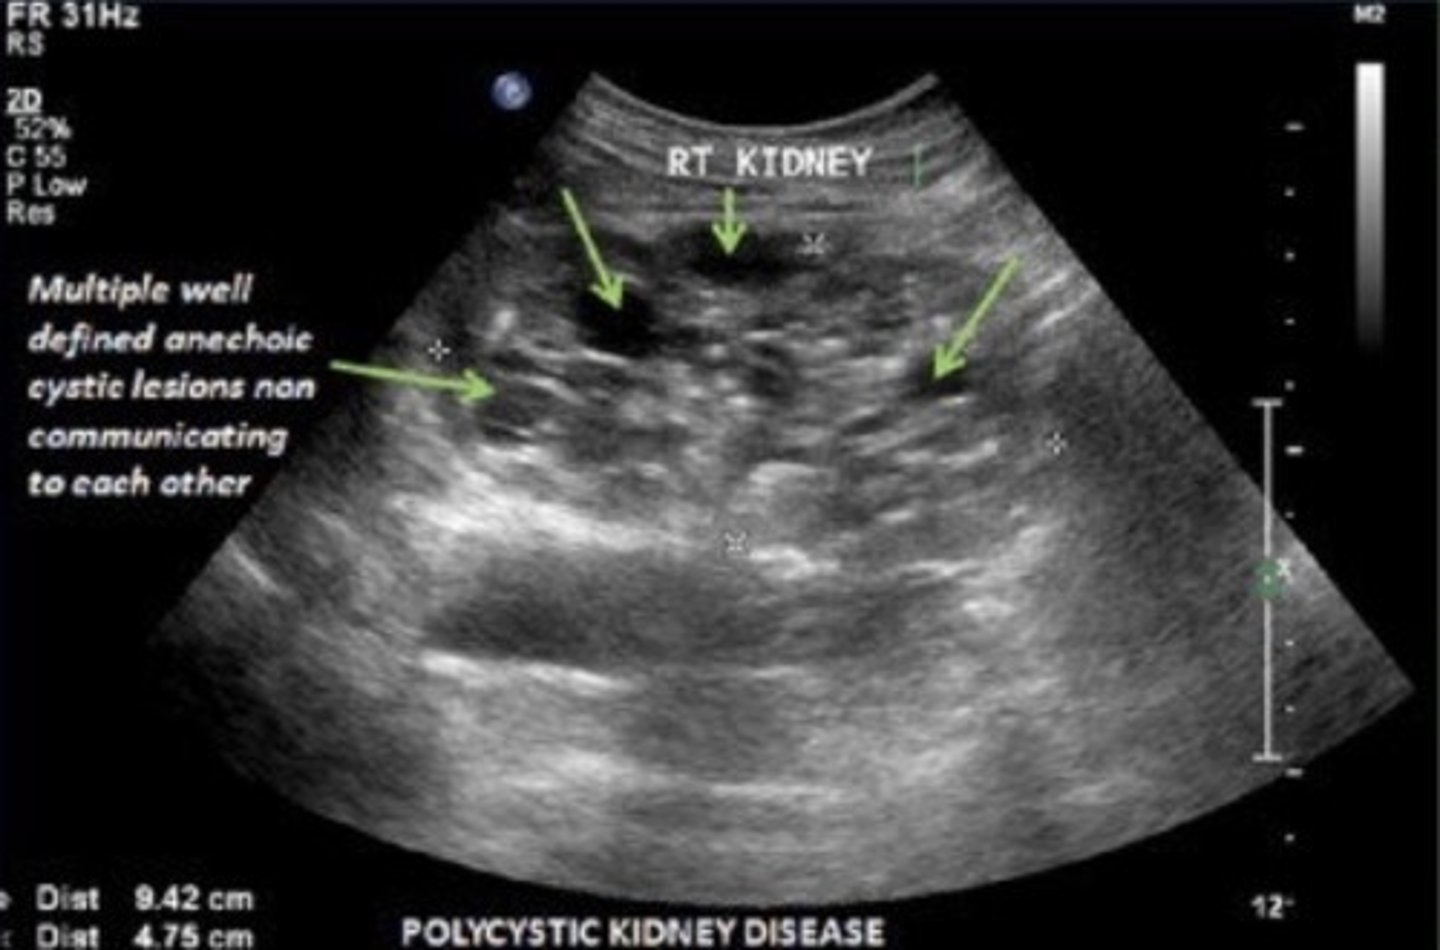

Potter's Syndrome Type I - Polycystic Kidney Disease

Bilateral micro cysts

Bilateral enlarged, echogenic kidneys

Empty bladder

Potter's Syndrome Type III - Autosomal Dominant Polycystic Kidney Disease

Bilateral large cysts

Large kidneys

Hyperechoic parenchyma

Normal bladder/fluid levels